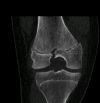

15 Y old, MVA, MFC # - Salter Harris III